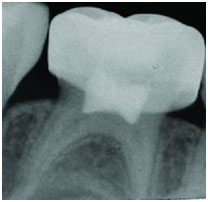

Una vez concluida la realización de la pulpotomía, la cámara pulpar se rellena y posteriormente se realizará una reconstrucción y/o se adaptará una corona de acero inoxidable. El objetivo será conseguir un buen sellado para impedir el anidamiento bacteriano y restaurar la forma y función de la pieza dental afectada.